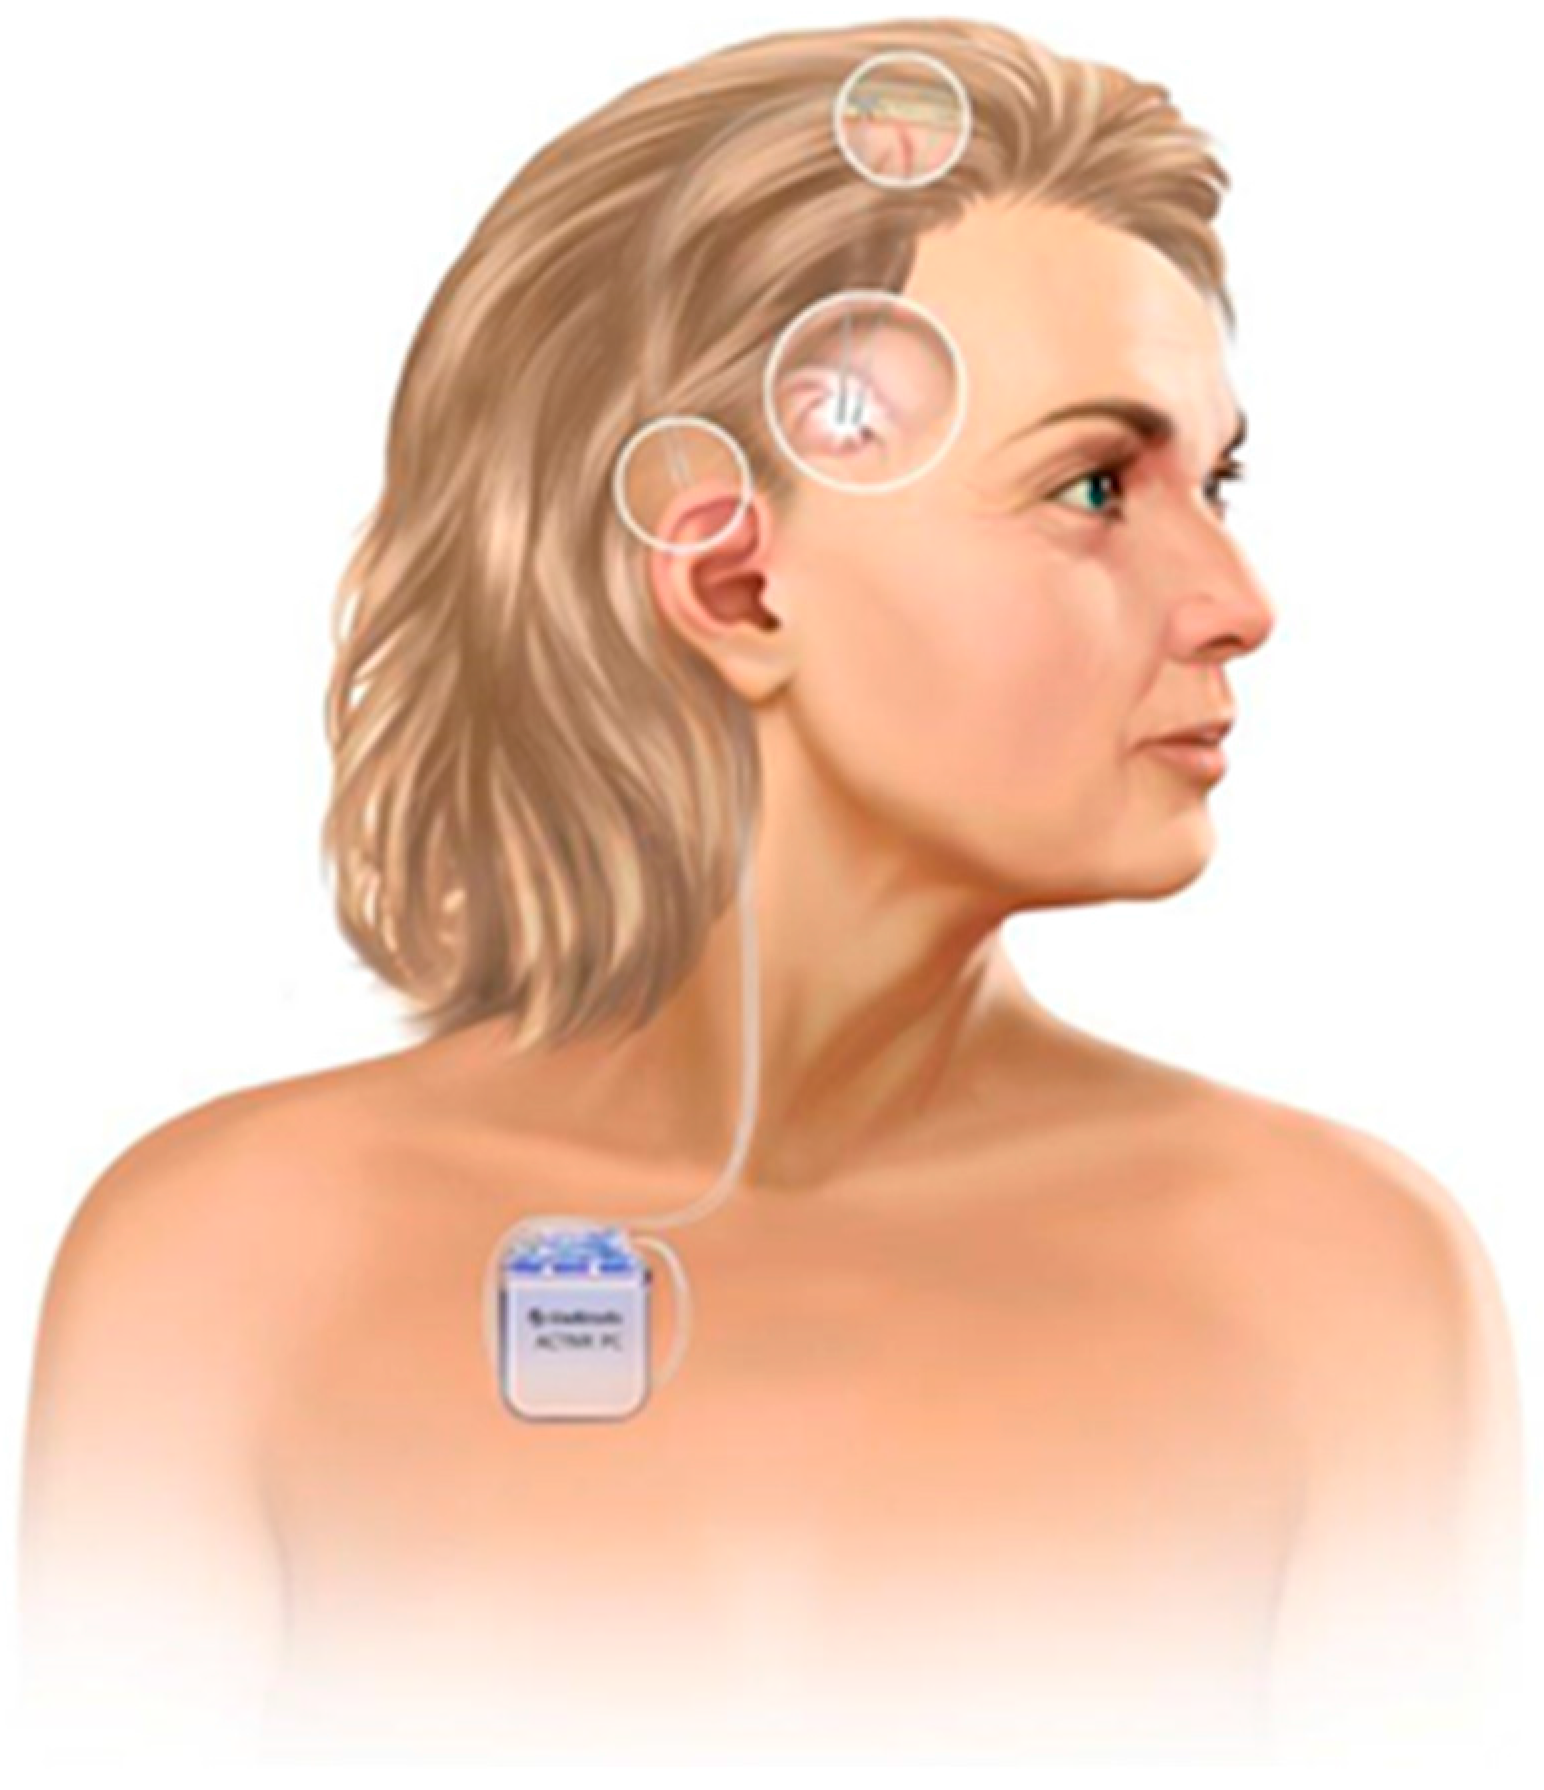

2. Evolution of Deep Brain Stimulation for HD